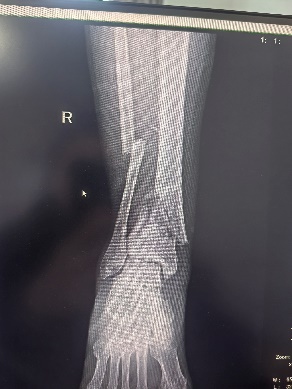

患者55歲男性,高處墜落致右側小腿腫痛伴活動受限,影像檢查顯示脛腓骨下端骨折,行機器人輔助下復位及外固定架固定。